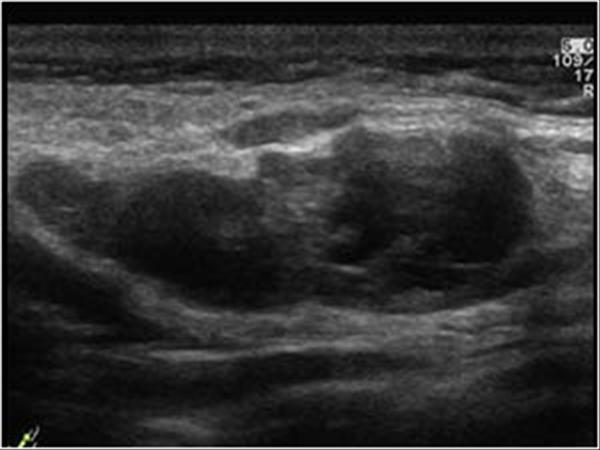

U tuyến nước bọt

» Thông tin: Nam giới – 64 tuổi.

» Lâm sàng: Khối vùng mang tai.

# U lympho tuyến nang (U Warthin) tuyến nước bọt mang tai.